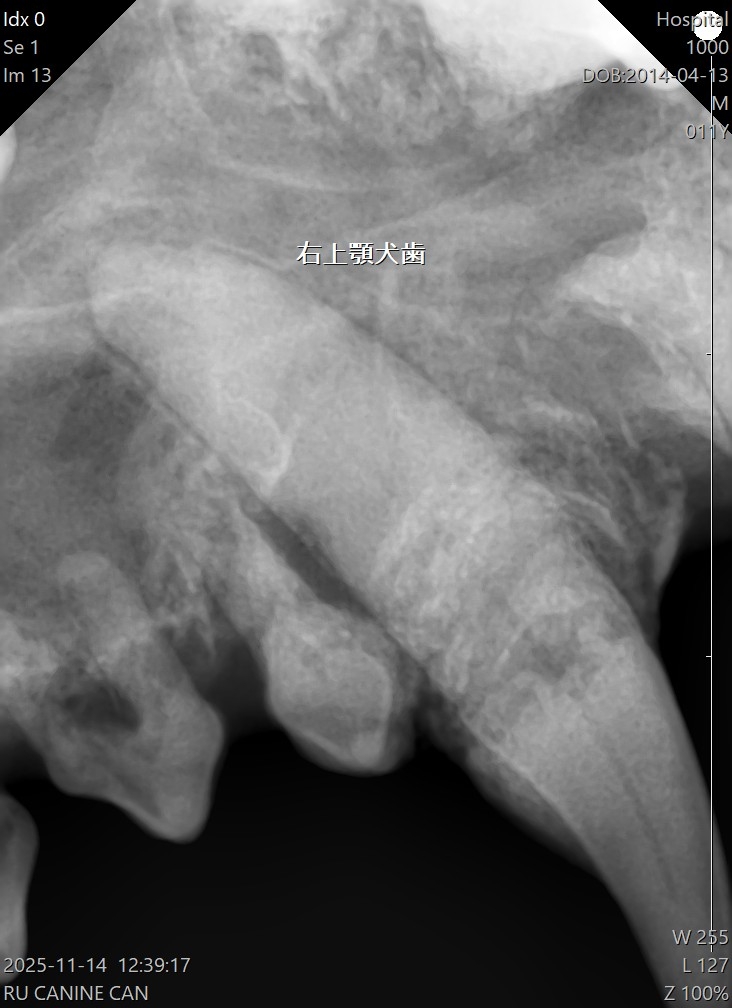

歯周ポケットの確認や歯科レントゲン撮影は、口腔内にブローブを入れるため 基本的には術直前に全身麻酔下で行います。

Lちゃんの場合歯周病の進行が著しく、既にぐらつきがあるもの 外見ではわからなかった歯根の周りの顎の骨が溶けている部分もレントゲンで確認できました。